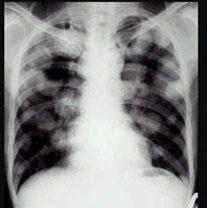

问题 男,45岁,HBV阳性十年,胸痛一月伴咳嗽,咯血一天,胸片如图,选择最可能的诊断 ( )

选项 A、金葡菌感染 B、肺转移癌 C、肺韦格肉芽肿 D、HBV病毒肺部转移 E、肺多发性脓肿

答案 B